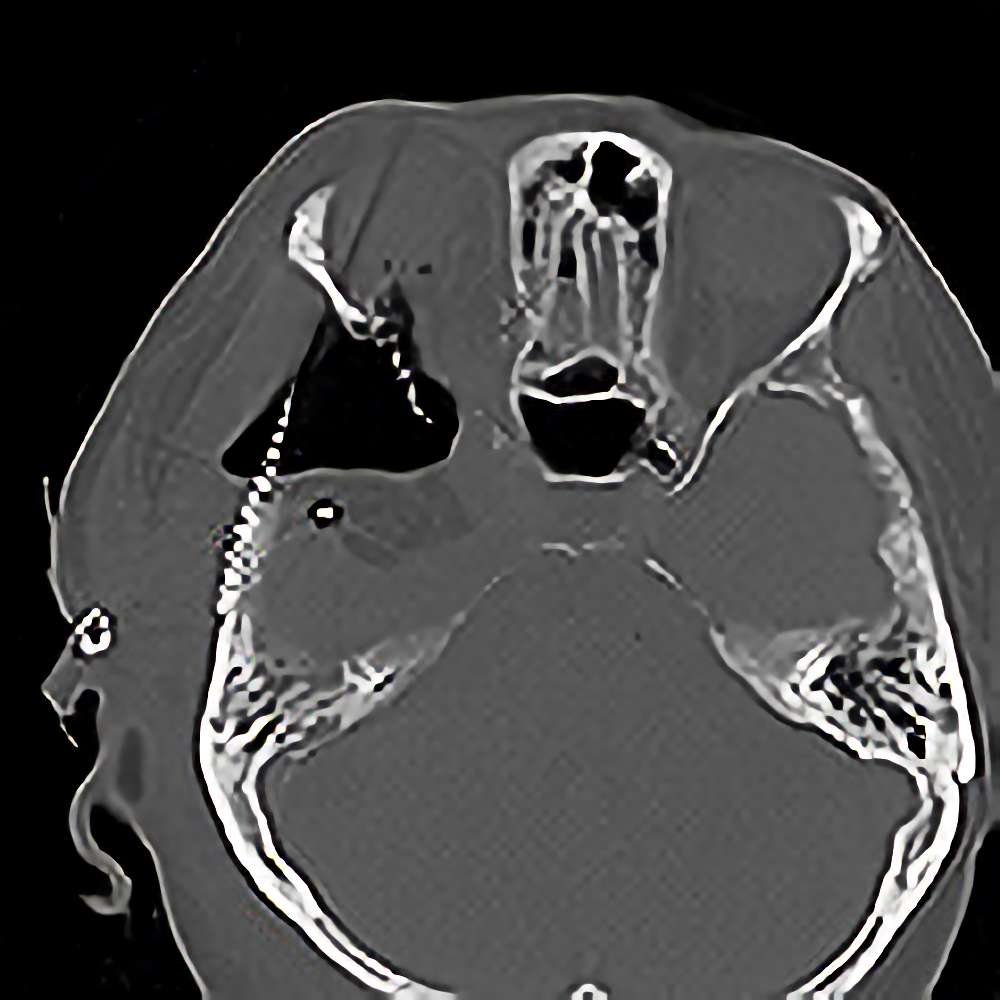

髄膜腫

(蝶形骨稜)

断層撮影

手術前1

No.’12_151 手術前1